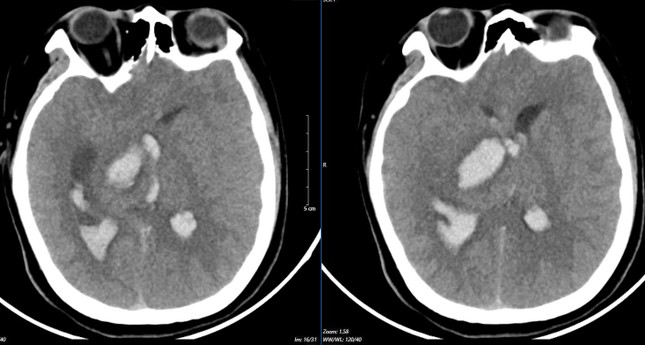

Hình ảnh chụp phim MSCT mạch não chảy máu não đồi thị - não thất do vỡ khối AVM (dị dạng thông động- tĩnh mạch não) bệnh nhân 15 tuổi. Ảnh: Bệnh viện Bạch Mai

Tình trạng khi vào Trung tâm Đột quỵ, Bệnh viện Bạch Mai: Ý thức hôn mê sâu, Glasgow 5 điểm, thở máy, giãn đồng tử bên phải. Kết quả chụp lại phim MSCT mạch não chảy máu não đồi thị - não thất do vỡ khối AVM (dị dạng thông động- tĩnh mạch não) biến chứng giãn não thất cấp, rối loạn thân nhiệt, sốt cao liên tục 39 - 40 độ C. Khối dị dạng mạch não tuy không quá lớn nhưng ở vị trí cực kỳ nguy hiểm . Mặc dù đã được hồi sức tích cực tại Trung tâm Đột Quỵ nhưng tình trạng diễn biến nhanh, bệnh nhân tụt huyết áp, thiểu niệu, rối loạn thân nhiệt, hôn mê sâu Glasgow 3 điểm. Sau 2 ngày điều trị, khi được bác sĩ giải thích không còn khả năng cứu chữa, gia đình đưa bệnh nhi về và bệnh nhi đã tử vong sau đó.